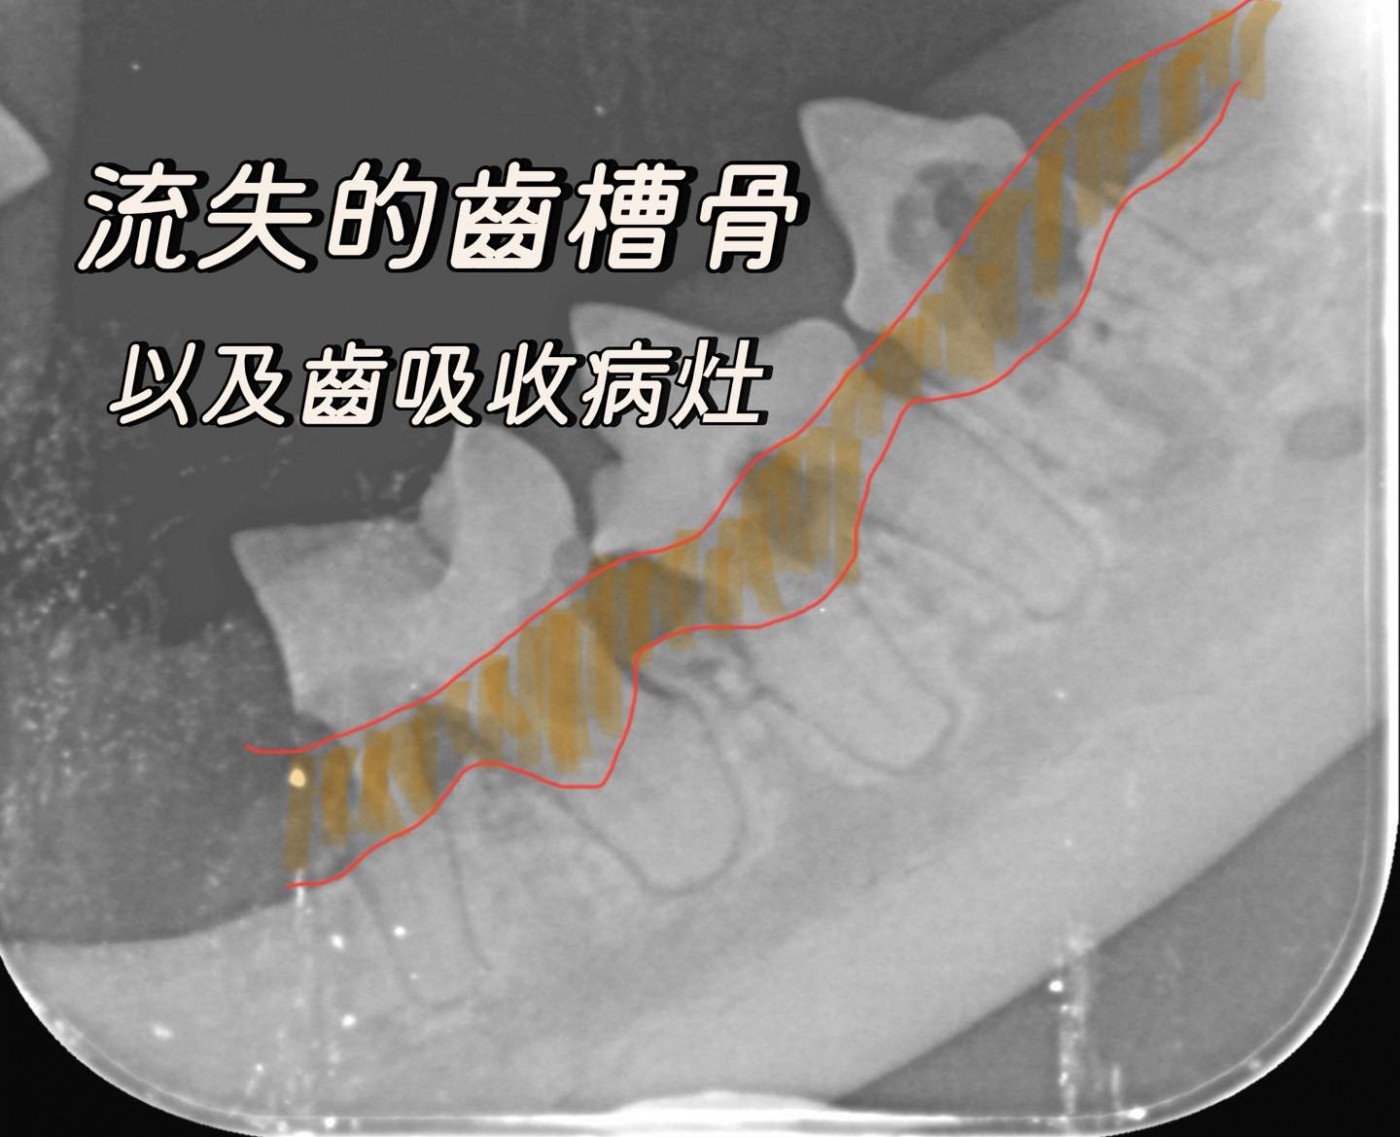

1. 發現隱藏的疾病 動物的牙齒表面可能看起來健康,但X光下卻看到膿瘍、齒槽骨流失、牙齒斷裂、阻生齒或齒吸收病變。避免錯誤診斷,進而導致動物必須在短時間內,再次被麻醉處理上一次本就該被治療的牙齒疾病。

3. 評估牙根與顎骨健康 許多牙科疾病影響牙根及周圍的骨骼,如牙周病。X光能評估完整牙周狀況,判斷牙齒是否可以保留,或是否有更深層的感染需要治療。